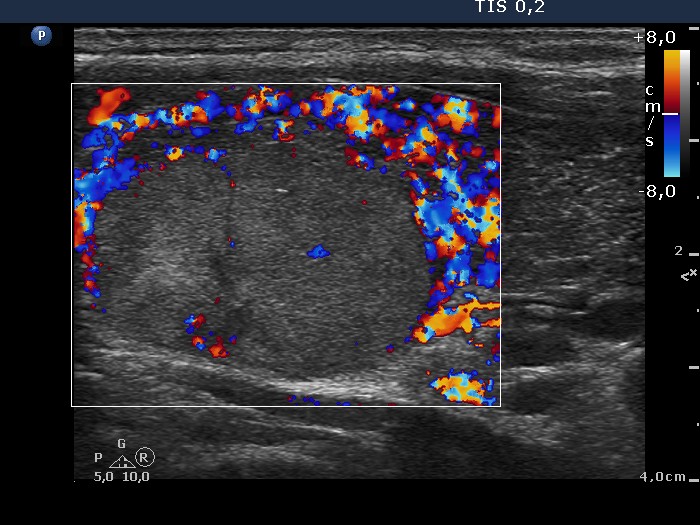

Consecutively operated patients with autoimmune thyroid disease - case 37 (conp 033) (ultrasonographic picture 9)

Left lobe, longitudinal scan, color Doppler mode. The presence of a perinodular blood flow can be judged only on the dorsal part of the nodule which lacks circulation, therefore we can state that the nodule displays neither perinodular nor intranodular blood flow.